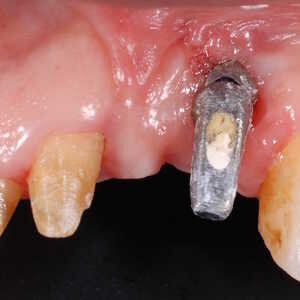

Dans cet article, nous présentons un cas clinique qui montre comment une mauvaise mise en place d'un implant peut rendre impossible la réhabilitation prothétique, ce qui nécessite une nouvelle planification chirurgicale et de réhabilitation pour obtenir l'esthétique souhaitée. Le patient se présente à notre observation avec une réhabilitation prothétique incongrue, avec bride en résine, support dentaire et implantaire, avec la présence d'un implant en position 2.1 vestibulaire et avec l'émergence dans le fornix, dans la mucosa alvéolaire. L'évaluation de la tomodensitométrie montre la position incorrecte de l'implant et la perte constante dans le sens transversal de la structure osseuse (Figs. 1, 2). Par conséquent, le plan de traitement suivant a été choisi : retrait de l'implant et préparation prothétique de l'élément 2.3, fabrication d'un premier support dentaire temporaire pour guider la cicatrisation des tissus (Figs. 3-7). Après 4 mois, une greffe d'épithélium conjonctif libre est réalisée avec ablation du palais pour compenser l'espace transversal des tissus mous, puis le provisoire est remodelé afin de faciliter la cicatrisation des tissus (Figures 8-11). Après 9 mois de maturation des tissus, la finalisation prothétique fixe avec support dentaire est réalisée (Figs. 12-14).